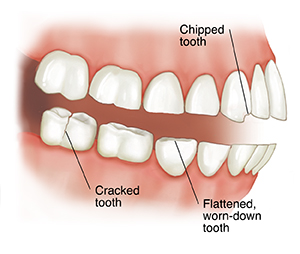

Damage caused by teeth grinding

Teeth grinding may cause:

Chipped enamel and cracked teeth.

Flattened, grooved, worn-down teeth.